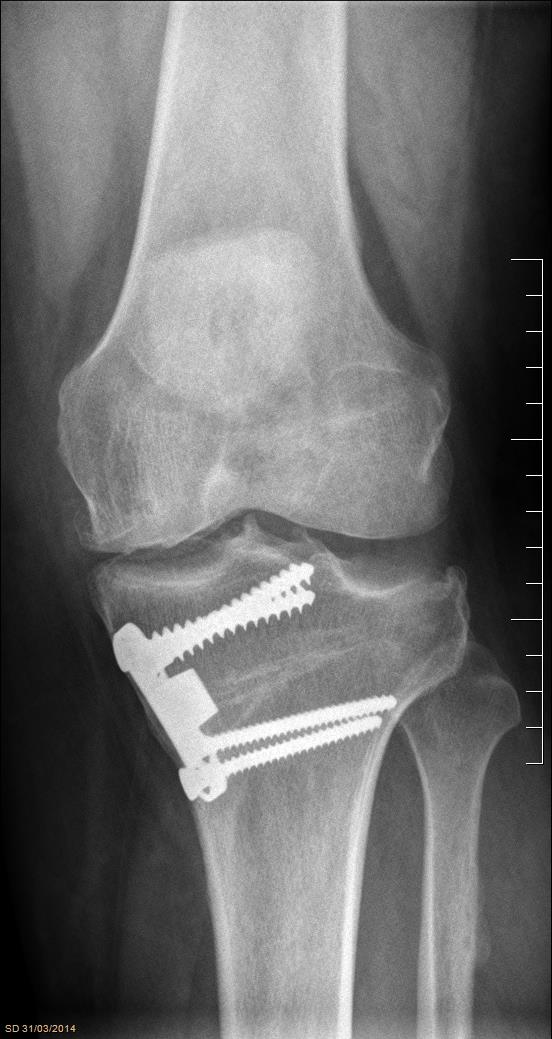

IntroducciónEl trasplante osteocondral autólogo es una alternativa quirúrgica en lesiones focales del cartílago articular. El objetivo de nuestro trabajo fue evaluar una serie de 62 pacientes tratados con mosaicoplastía de rodilla con 8 años promedio de seguimiento.Material y métodosEvaluamos retrospectivamente 62 pacientes operados con mosaicoplastía entre el año 2001 y 2014. Se incluyeron pacientes con lesión de cartílago focal de la rodilla a los que se les realizó mosaicoplastía aislada o asociada a otros procedimientos quirúrgicos (reconstrucción de LCA, osteotomía). Con un seguimiento mínimo de 2 años. Se evaluaron con las escalas de Lysholm e IKDC y el grado de artrosis con la escala radiográfica de Kellgren-Lawrence.ResultadosCuarenta y cinco fueron hombres y 17 mujeres. La edad promedio fue de 36 años. Treinta y cinco en cóndilo interno, 12 cóndilo externo, 12 tróclea y 3 combinadas. Cuarenta y dos fueron mosaicoplastías aisladas y 20 asociados a otro procedimiento. El resultado promedio de la escala de Lysholm al momento de la evaluación fue 80.1 y el IKDC fue 66.7. No encontramos diferencias significativas en la escala de Lysholm e IKDC entre los grupos de mosaicoplastía aislada y asociada a otro procedimiento. En 30 pacientes evaluados con radiografía se observó una inclusión satisfactoria del taco óseo.ConclusionesDentro de las opciones quirúrgicas se encuentran las microfracturas, el auto/alo injerto osteocondral y el implante de condrocitos autólogos. Todas estas técnicas han demostrado mejorar el estado clínico en comparación con el estado preoperatorio independientemente de cuál se utilice. En nuestra serie de pacientes operados con mosaicoplastía encontramos resultados satisfactorios en las evaluaciones clínicas.Consideramos que la mosaicoplastía es un procedimiento con alto grado de satisfacción y buenos resultados funcionales en pacientes con lesiones focales del cartílago articular. AbstractIntroduction: Osteochondral autograft transplantation is a surgical alternative for osteochondral defects of the knee. The aim of this study was to analyze a series of 62 patients treated with osteochondral autograft transplantation of the knee and an average follow-up of 8 years.Methods: A total of 62 patients treated with osteochondral autograft transplantation between 2001 and 2014 were evaluated. Patients with focal osteochondral lesions who underwent osteochondral autograft transplantation alone or associated with another procedure and a minimum follow-up of 2 years were included. Lysholm score, IKDC, and Kellgren- Lawrence radiographic scale were used. Forty-five men and 17 women (average age 36 years) were evaluated. Lesions were localized in medial condyle (35), lateral condyle (12), patella (12), and three were combined. Forty-two patients underwent isolated osteochondral autograft transplantation while 20 patients underwent associated surgical procedures.Results: Mean Lysholm score was 80.1 and IKDC score was 66.7. There were no significant differences in the Lysholm and IKDC scores between groups. Radiographic results demonstrated complete graft incorporation in 30 patients. Clinical evaluation revealed satisfactory results.Conclusion: Osteochondral autograft transplantation to treat osteochondral lesions is a procedure with a high clinical satisfaction and good functional results in patients with focal osteochondral lesions.Descargas